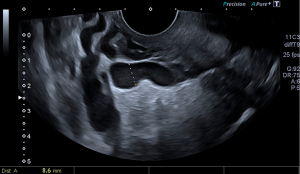

The selected model was Model 3, which identified the presence of a pelvic vein or venous plexus of 8 mm or greater, as predictor of the venographic diagnosis of PCS. Model 3’s Harrell’s C-index obtained from the AUC of the predicted probabilities was 0.79 (95% CI: 0.63–0.96; P<0.001), with a sensitivity of 0.90 and specificity of 0.69 (Figure 2). Table 4 displays the contrast between Model 3 and the gold standard, which shows a sensitivity of with a sensitivity of 86.05%, a specificity of 66.67% and a positive predictive value of 86.05% (Table 5). Ultrasonography captions of the measurement of pelvic vein and venous plexus are displayed in Figures 3,4.

Ultrasonography evaluation was carried out by an expert in gynecological ultrasound, with more than 15 years of experience, using a Canon Aplio 500 (Toshiba Medical systems Corp., Tokyo, Japan) with a 6.5 MHz probe. Set-up of the 2-D mode consisting in the use of 2 focal zones, with an 80–95 gain, dynamic range of 60–75. For the use of color and spectral Doppler the size of the Doppler sampling window was set at 45×45 mm, color gain between 35–45 and PRF at 5.4–7.6 cm/s. In order to carry out the examination while the bladder was empty, as is customary, patients were asked to adopt the gynecological position short after urinating. The assessment started first by completely assessing the uterus and the adnexa in a longitudinal and cross-sectional plane. We used the simplified prolate ellipsoid formula to calculate uterine and ovarian volumes. Afterwards, the uterine vein was tracked from its origin at the internal cervical os up until the internal iliac veins and collateral branches, in order to identify the largest pelvic vein as well as the venous plexus. These were measured in their anteroposterior diameter in a cross-sectional plane. For the Doppler assessment of the pelvis, we identify the flow direction with color and spectral Doppler and asked the patient to perform a Valsalva maneuver to identify changes in the flow velocity. This procedure was first performed in one side and then repeated for the contralateral side. Subsequently, we applied color Doppler in a cross-sectional plane of the uterus determine whether there were crossing veins in the myometrium, then measured its maximum anteroposterior diameter. Thus, we collected the following ultrasonographic variables: uterine volume, right and left ovarian volume, presence of polycystic ovaries (PCO), inner diameter of the largest pelvic vein (right and left side), maximum diameter of the largest venous plexus (right and left side), reverse or altered flow during Valsalva, presence of crossing veins in the myometrium, and maximum diameter of crossing veins in the myometrium.